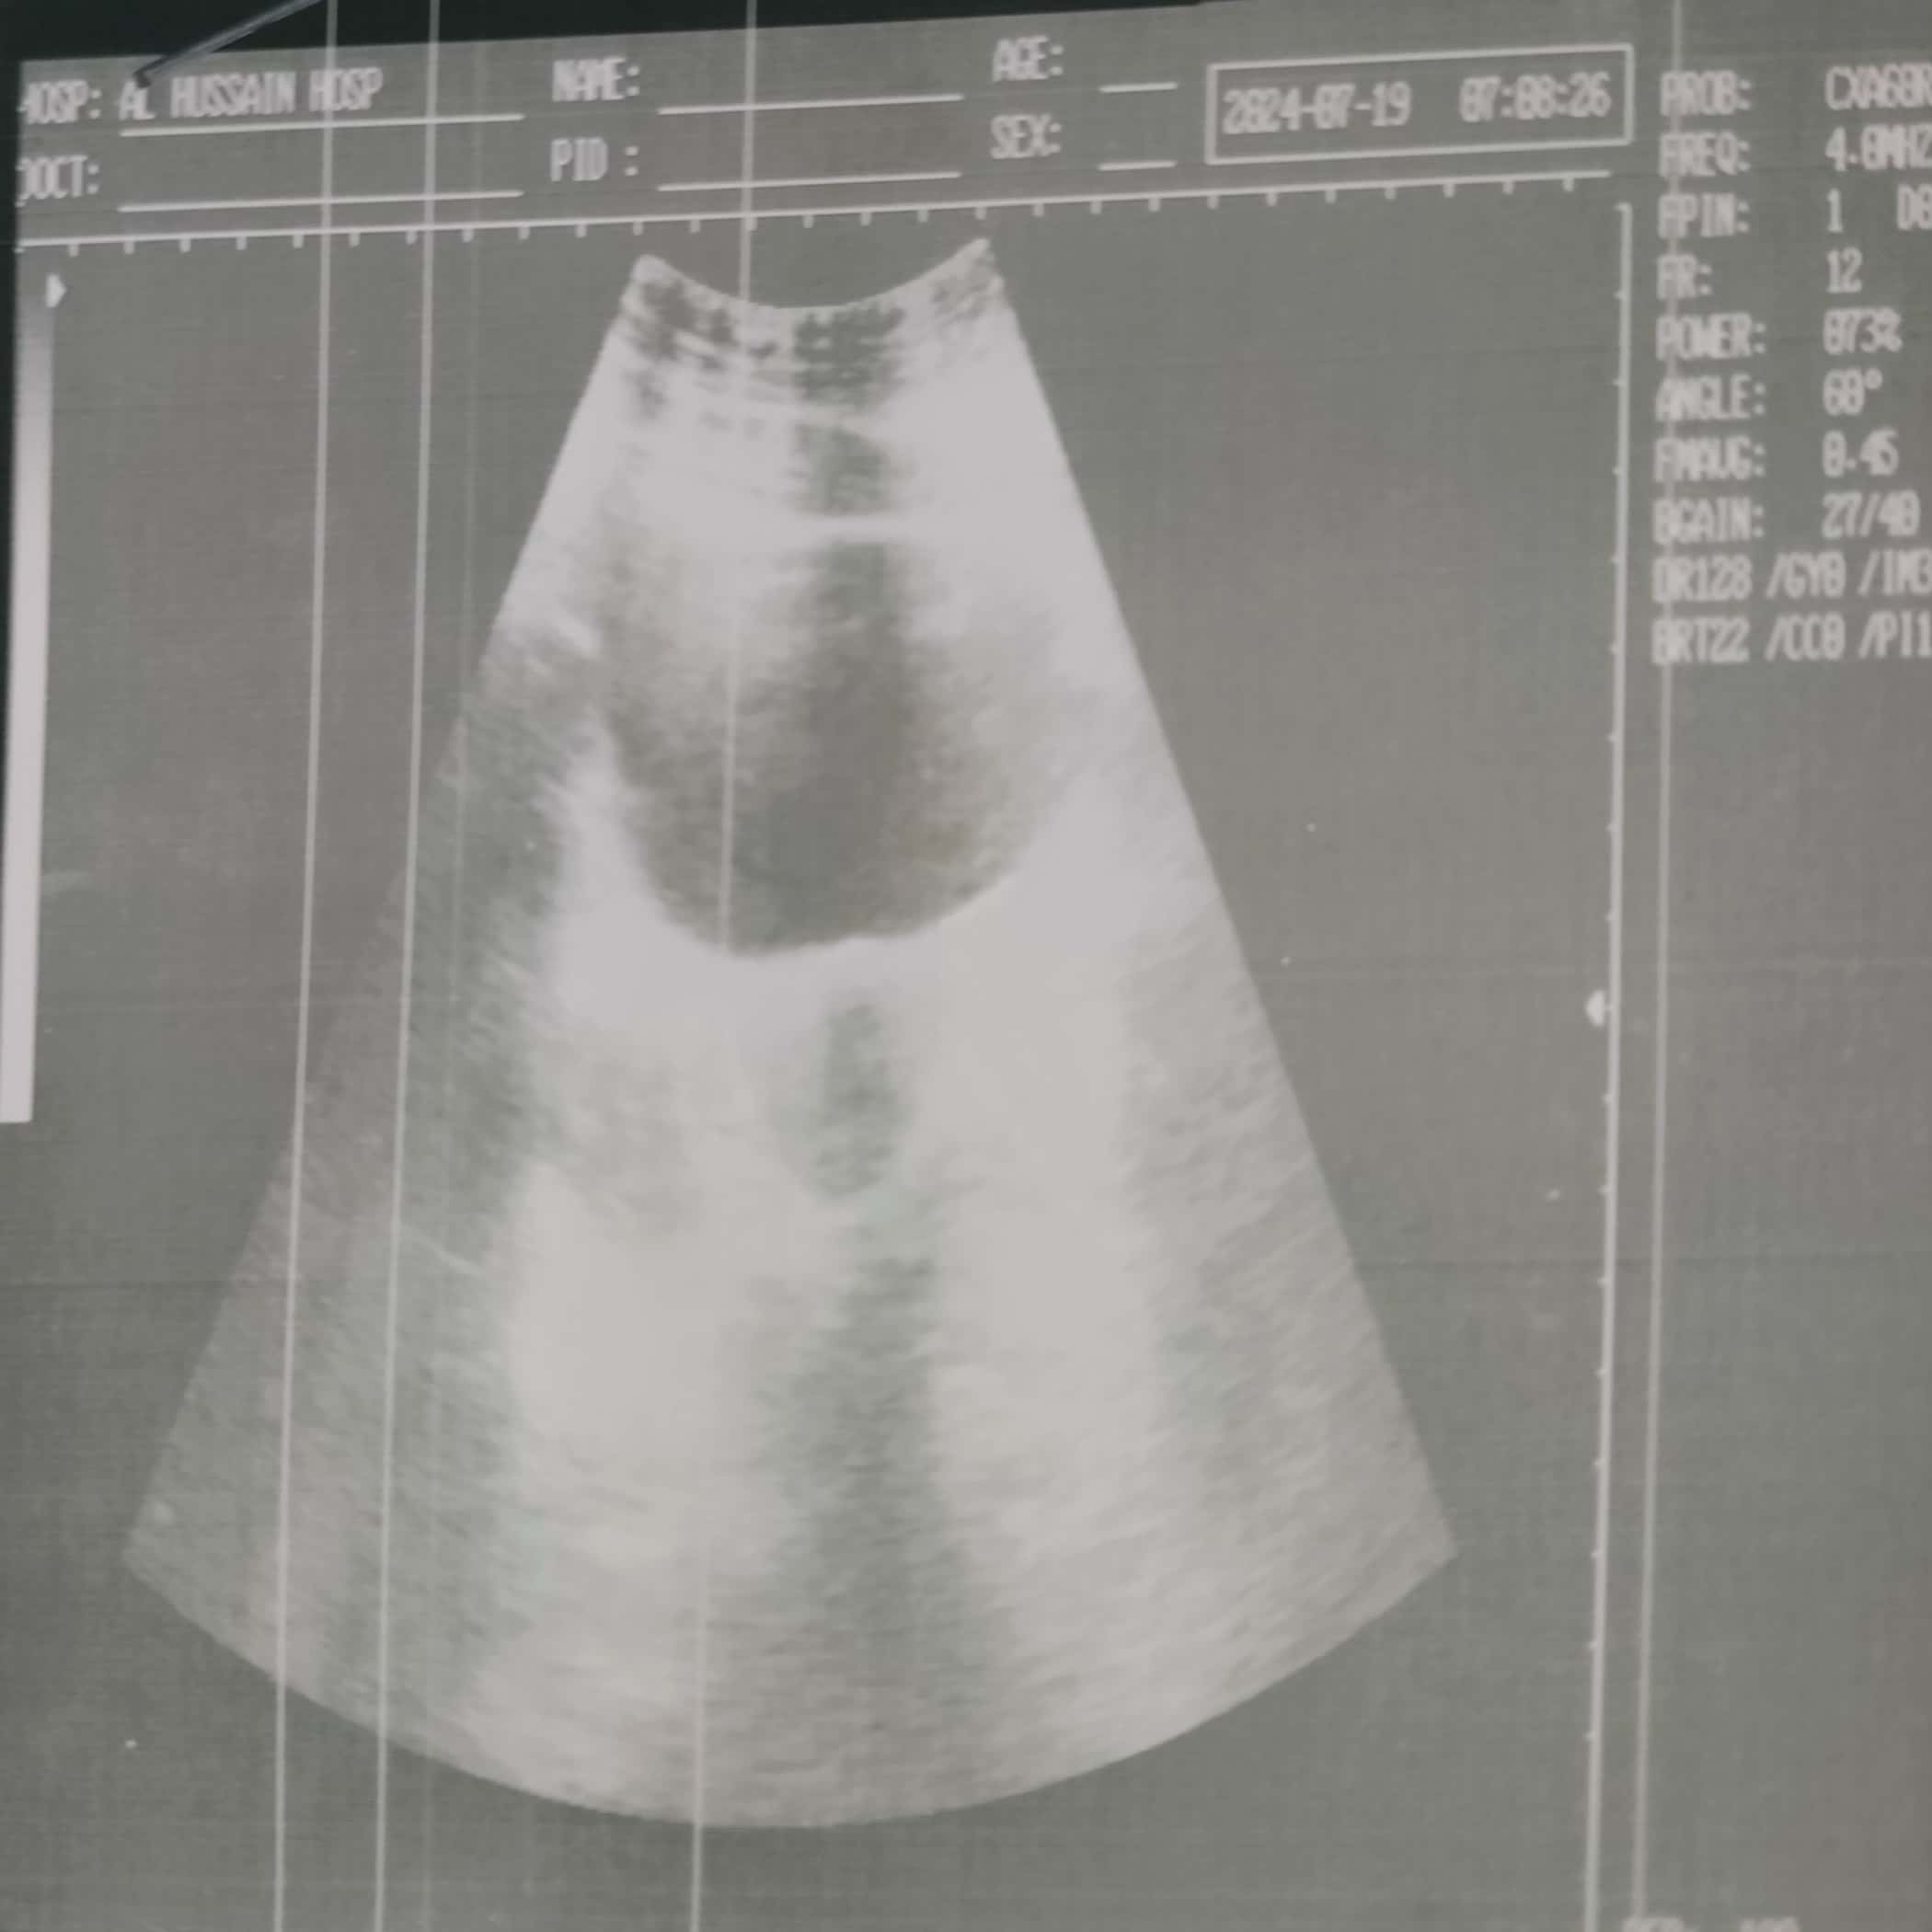

I am suffering from PCOS and have small cyst in my ovaries. Kindly review my reports given and let me know if should I continue to take glucophage 500mg? And is this curable? Is there nothing to worry?

These are my periods 2nd day ultrasound report..

These are my ultrasound reports

These are my ultrasound report

Here are my ultrasound reports

Ultrasound report

Dear you are suffering from severe pcos according to the reports… i have to evaluate you completely for detailed discussion kindly book your appointment i will give you a proper prescription for this . And don’t worry its a treatable disease..